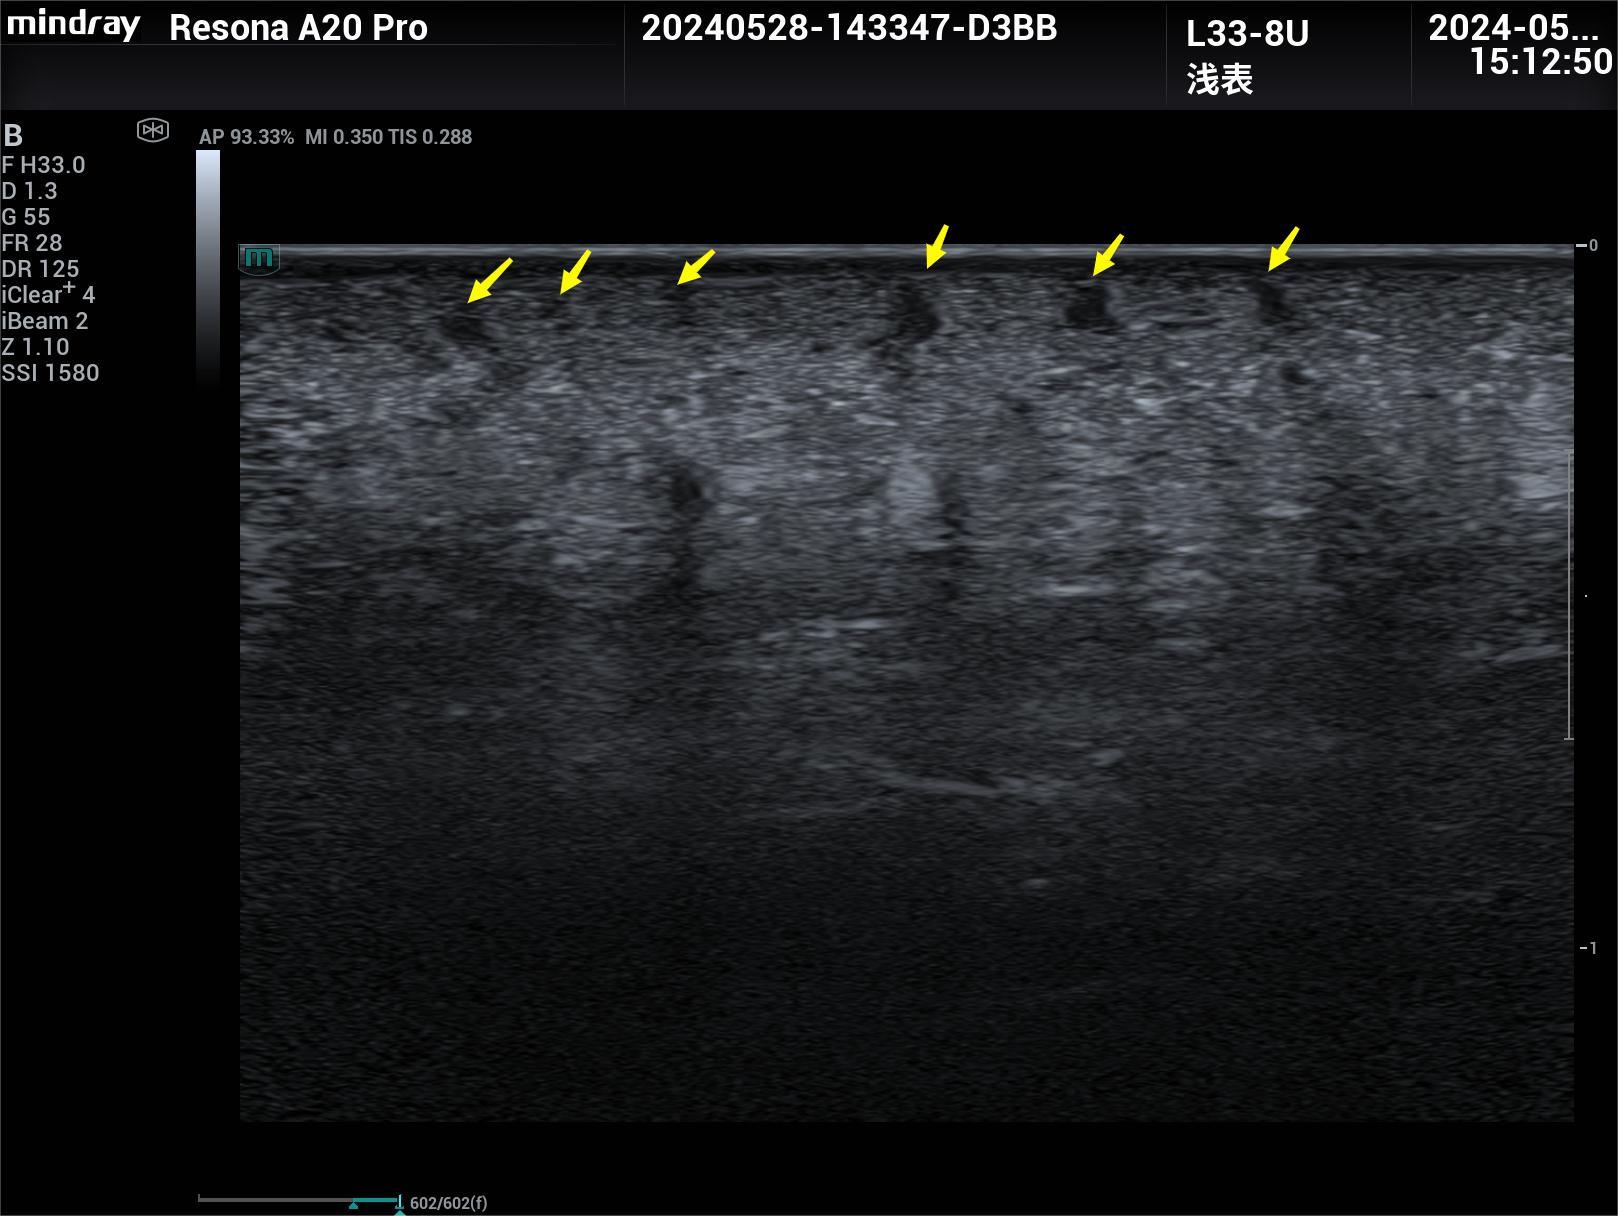

随着超声技术在微血管显像上的不断突破,继超声造影和超微血流成像技术之后,在商业化超声诊断设备上这两年出现了一种新的微血管成像技术----显微造影成像技术,该技术结合超声造影和“光学荧光识别定位技术”,利用超高帧率捕捉和跟踪超声造影剂微泡的运动轨迹,呈现组织和病灶微血管架构,该技术突破了超声理论分辨率的限制,实现了微米级别的显示,能够呈现和定量10-100微米的血管,对微循环的距离指标、血管密度、灌注情况、血管复杂情况、血流动力学情况等提供了丰富的定量参数,这一突破为我们的临床研究提供了广泛的、全新的领域和方向。